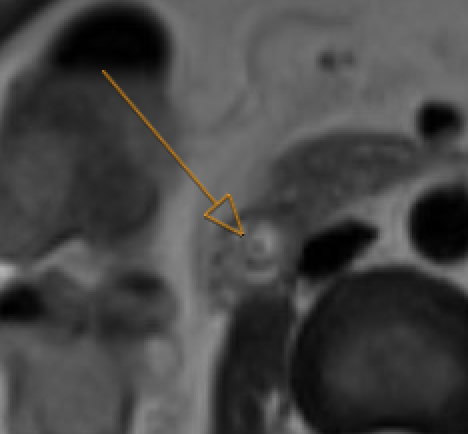

Choledocholithiasis T2-hypointense filling defect in bile duct on MRCP. Obstructive: upstream dilatation, abrupt caliber change. Trace entire biliary system on thin MRCP/T2W

MRCP showing T2-hypointense filling defect in common bile duct consistent with choledocholithiasis

Choledocholithiasis: T2-dark filling defect (arrow) on MRCP

GB neck and cystic duct are blind spots. Pneumobilia can mimic calculi (nondependent, blooms on GRE). Crossing vessel on coronal MRCP can mimic filling defect — check axial reformats